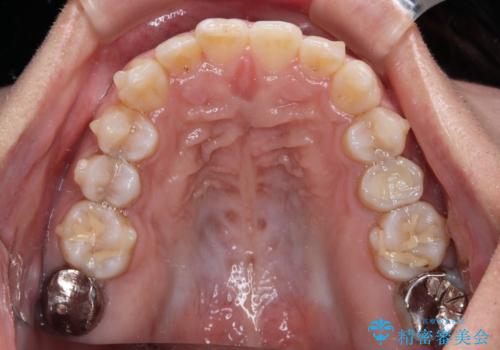

- 上下前歯の叢生を気にして来院された患者様です。

軽度な叢生であり、安価で短期間の治療を規模されていたため、インビザライン・モデレートを用いて矯正治療を行うこととしました。

インビザライン・モデレートは、製作できるアライナーの枚数に制限があるため、移動可能な量に限りがあるものの、インビザライン・ライトよりも枚数が多いため、幅広い症例に対応可能です。